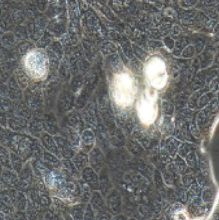

中文名称:人肺腺癌细胞

简称:Calu-3

形态:上皮细胞样

背景资料:该细胞是从一名25岁的白人男性肺腺癌患者的胸水中分离建立的;该患者曾使用过环磷酰胺、博来霉素、阿霉素进行治疗。该细胞接种至裸鼠可成瘤;可作转染宿主。